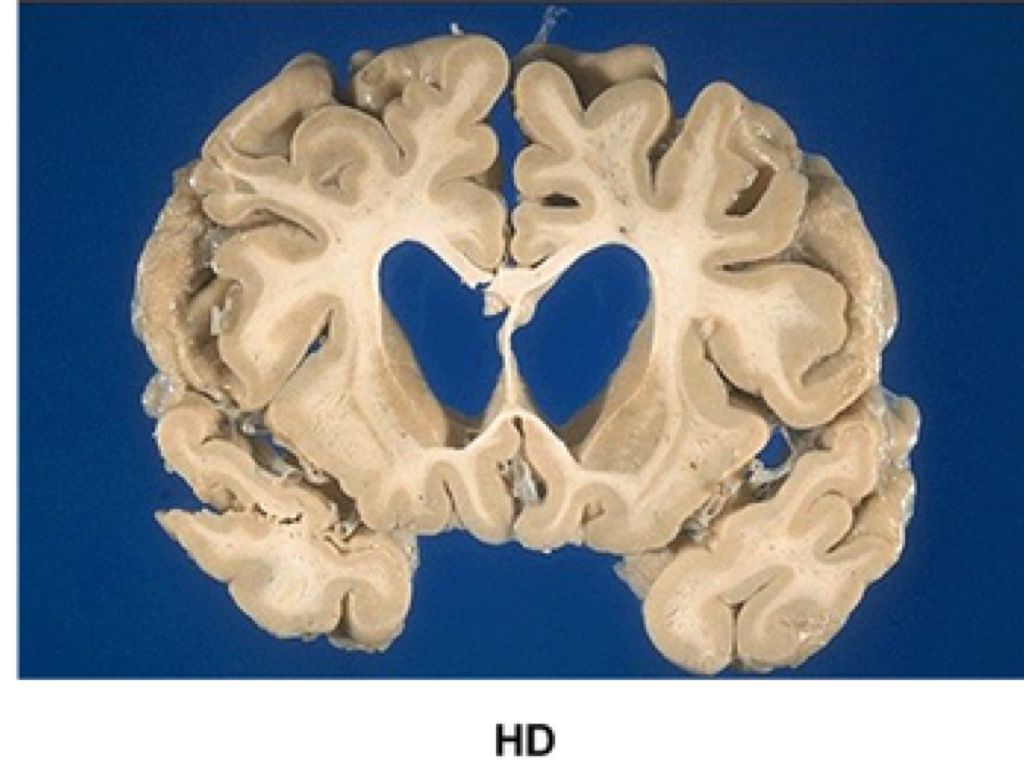

WHAT IT IS

Huntingtons disease/Huntington's chorea is when mutated genes are programmed to degenerate nerve cells in the brain.